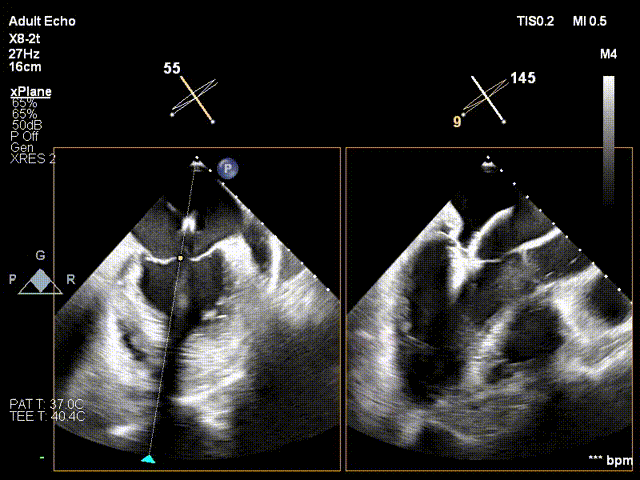

4. 打开夹持臂,调整Orientation后着陆,夹合后隔交界

夹合

6. 第二套器械同样操作 夹合前后交界

同样操作